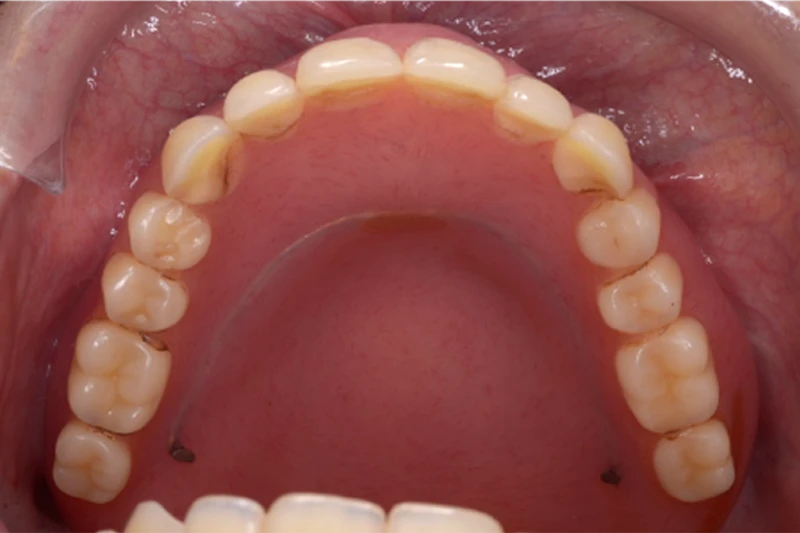

治療前

主訴 むし歯を治したい、入れ歯で咬めない

期間 10カ月

治療回数:20回

費用 ¥1,815,000

治療内容 ・プロビジョナルレストレーション作成

・隔壁作成、精密再根管治療、ファイバーポストコア

・精密印象採得、クラウン試適、セラミッククラウン装着

・精密印象採得(義歯)、咬合採得、義歯試適、金属床義歯装着

治療に伴うリスク ・想定を超える力が加わった際に割れる恐れがあります。

・咬み合わせのチェック、クリーニングによるメインテナンスを行う必要があります。